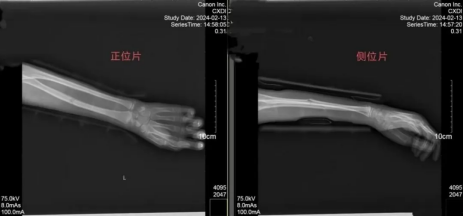

复位后经检查,李某骨折处对位、对线良好,骨折断端成角、移位得到纠正,成功复位。

患者手法复位后检查显示骨折处移位得到纠正